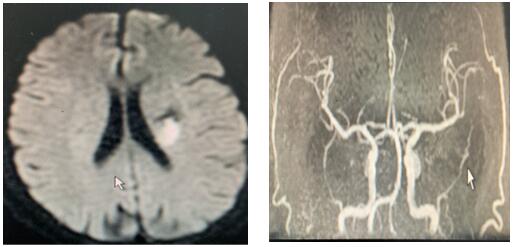

患者治療前影像圖

戰(zhàn)疫情,防卒中,我們刻不容緩!2020年2月14日,同往常一樣,卒中中心接診一名65歲患者,突發(fā)右側(cè)肢體活動不靈,卒中急診張帆醫(yī)師迅速判斷,考慮急性缺血性腦卒中,在NICU王偉偉副主任帶領(lǐng)下反復排查新型冠狀病毒感染,溶栓治療工作有條不紊,張沖醫(yī)師嚴密觀察患者生命體征,溶栓效果及不良反應(yīng),治療后右側(cè)肢體肌力恢復4級,基本生活自理,達到溶栓效果。這是我們工作的常態(tài)!無論疫情是否,我們卒中人始終堅守一線,從進入NICU,一直到他們帶著笑容走出大門,那一張張笑臉是我們繼續(xù)堅持的動力!